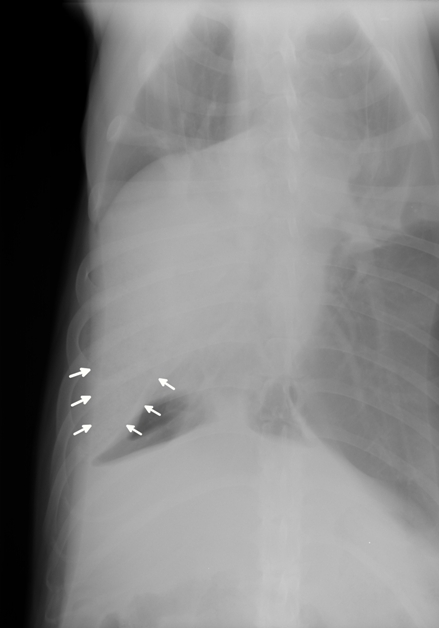

Each bronchus should try to be identified on each radiographic view. An air bronchogram is visible within the opaque lobe. Of those three the pulmonary parenchyma typically poses the greatest. Ventrodorsal thoracic radiograph of a dog with bronchopneumonia involving the right middle lung lobe. Do you remember the normal anatomy of the canine and feline lung and which lung lobes form the cranio-ventral which ones the caudo-dorsal lung field.

Consolidation is usually more obvious than atelectasis in these patients ie there is usually no decrease in size of the affected lung lobes. B Right lateral radiograph of a 9-year-old mixed breed dog centered on the cranioventral lung lobes. Consolidation is usually more obvious than atelectasis in these patients ie there is usually no decrease in size of the affected lung lobes. Aspiration pneumonia generally implies acute lung infection that occurs after aspiration of oropharyngeal or upper gastrointestinal contents in large volumes. Knowledge of this arrangement or the lung fissures is important in recognition of pleural effusion or thickened pleura. Large deep chested dogs esp.

An air bronchogram is visible within the opaque lobe. The more contemporary standard of care is three-view thoracic and abdominal radiographic studies because of the. Obstruction of bronchus absorption. Right lateral radiograph dog. Normal radiological anatomy of the lung in dogs.